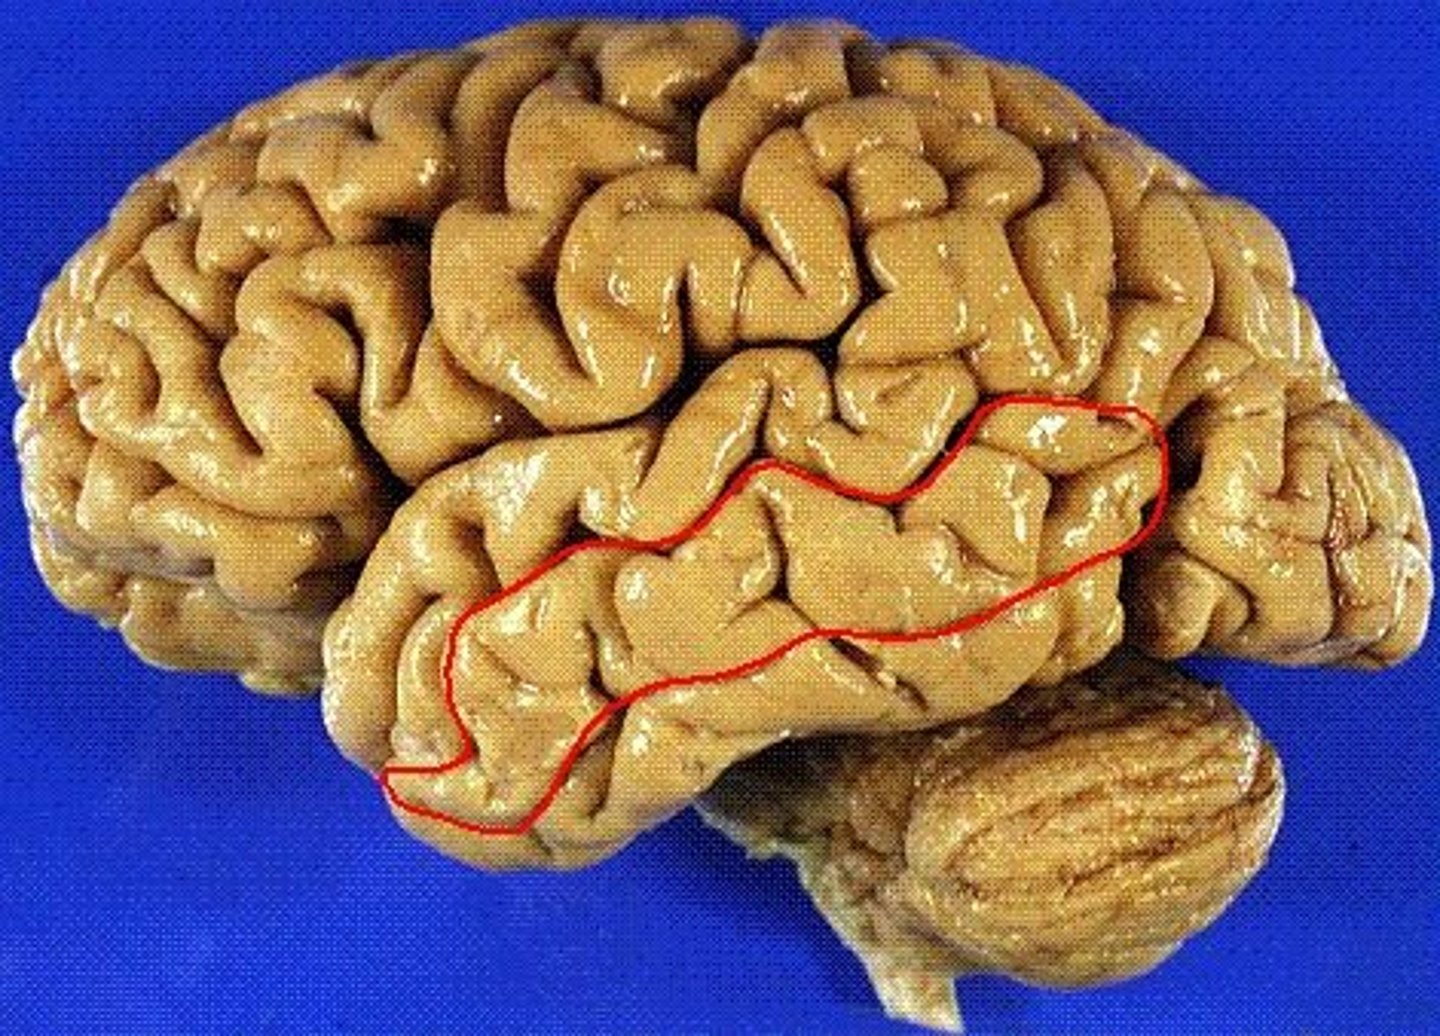

temporal lobe

A part of the brain located behind the ears that is crucial for processing auditory information, memory, emotion, and language. Contains three gyri parallel to the lateral fissure.

superior temporal gyrus

nearest to the lateral fissure. location of the primary auditory cortex.

middle temporal gyrus

the temporal lobe gyrus that is located between the superior and inferior temporal gyri

inferior temporal gyrus

the temporal lobe gyrus that is located just inferior to the middle temporal gyrus